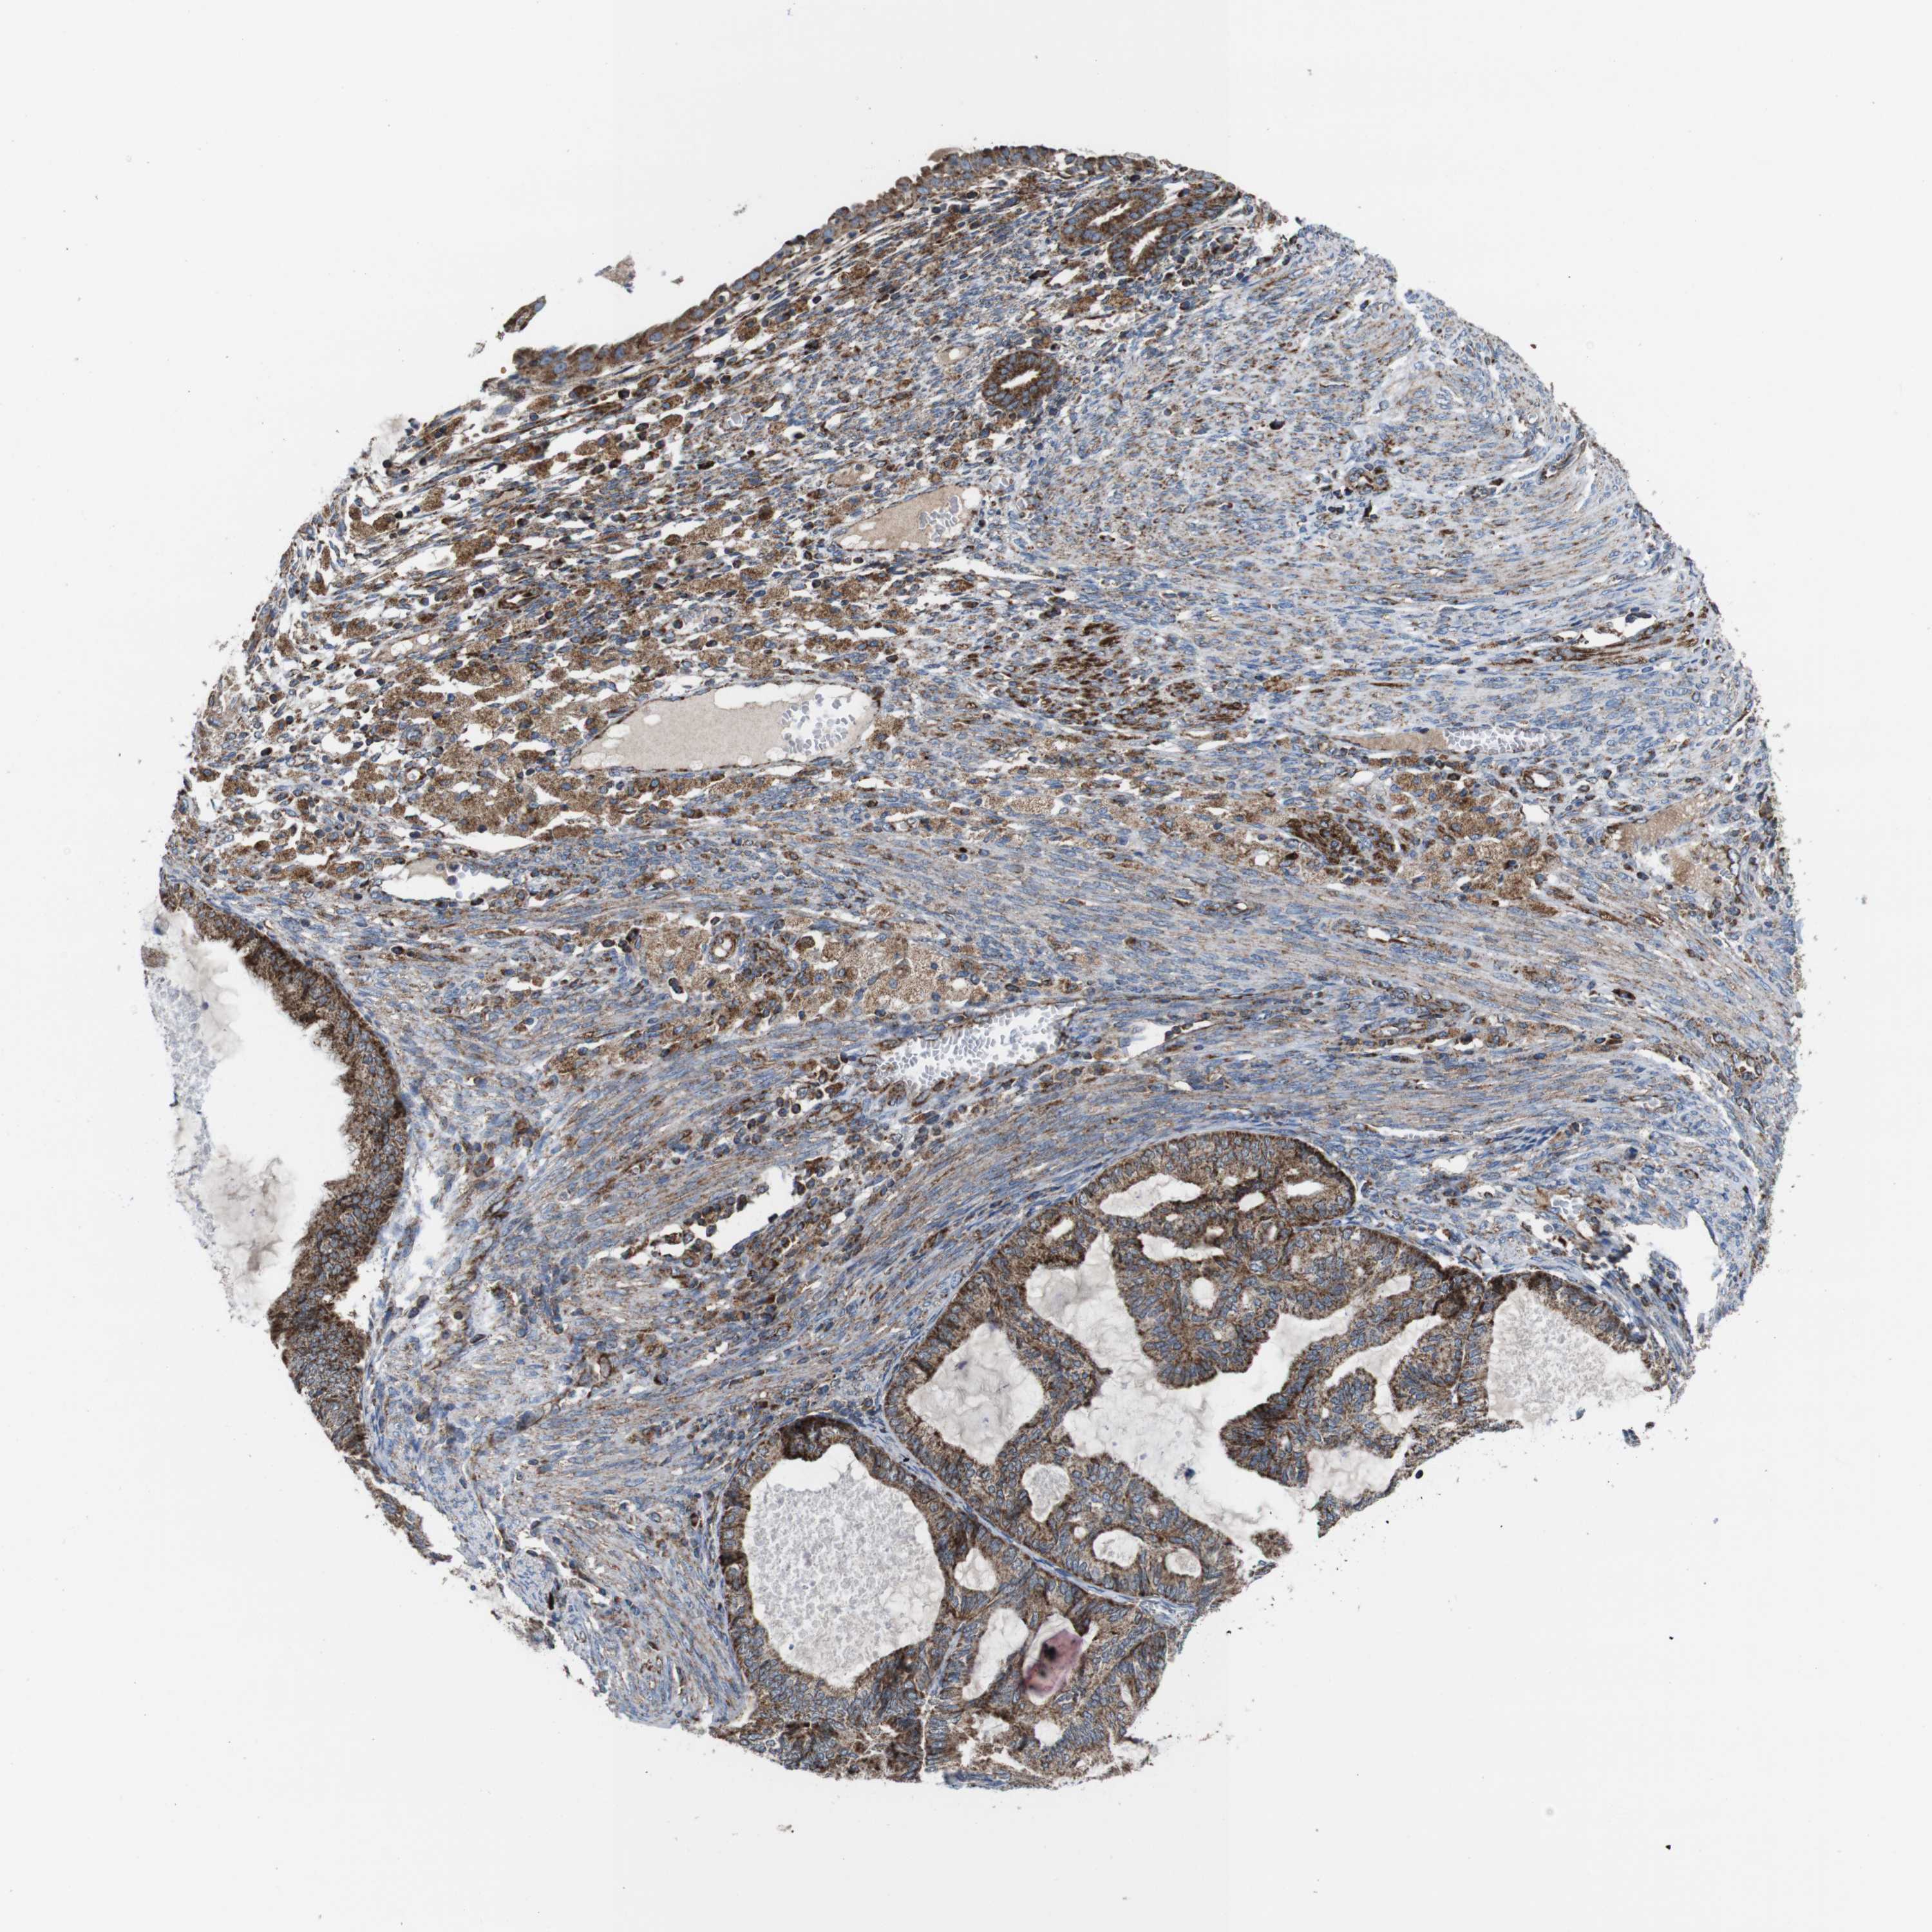

CERVICAL CANCER - Protein expressioni

A mouse-over function shows sample information and annotation data. Click on an image to view it in a full screen mode. Samples can be filtered based on level of antibody staining by selecting one or several of the following categories: high, medium, low and not detected. The assay and annotation is described here.

Note that samples used for immunohistochemistry by the Human Protein Atlas do not correspond to samples in the TCGA dataset.

Antibody stainingi

Antibody staining in the annotated cell types in the current human tissue is reported as not detected, low, medium, or high, based on conventional immunohistochemistry profiling in selected tissues. This score is based on the combination of the staining intensity and fraction of stained cells.

Each image is clickable and will lead to virtual microscopy that enables deeper exploration of all samples and also displays staining intensity scores, fraction scores and subcellular localization as well as patient and tissue information for each sample.

Antibody HPA007043

Antibody HPA007044

Antibody CAB010052

Staining

High

Medium

Low

Not detected

Intensity

Strong

Moderate

Weak

Negative

Quantity

>75%

75%-25%

<25%

None

Location

Nuclear

Cytoplasmic/membranous

Cytoplasmic/membranous,nuclear

Squamous cell carcinoma, NOS

Adenocarcinoma, NOS